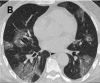

Figure 3a.

A-C. Non-contrast chest CT images of a 56 year old man with severe COVID-19 pneumonia. CT scans show multiple ground-glass opacities in multiple lung segments, the CT-SS is 28. D-F. Non-contrast chest CT images of a 69 year old man with severe COVID-19 …

Figure 3b.